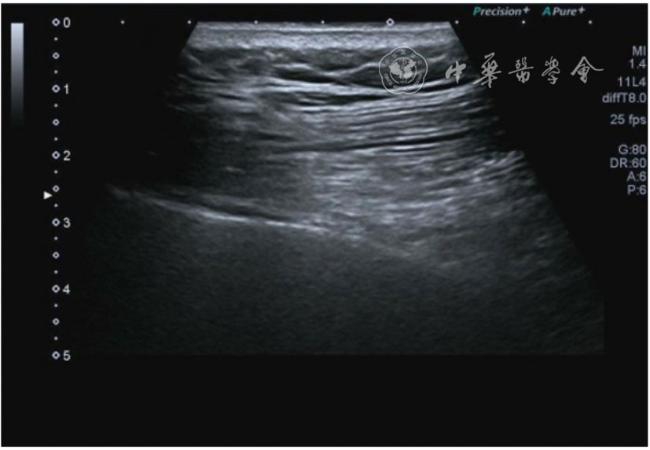

2.关节外表现。(1)副韧带损伤。内侧、外侧均可出现,但是内侧更常见。与膝内翻发生率高有关。超声可见副韧带增厚,回声不均匀,血流增加。半月板突出时可见韧带凸起移位(图7)。(2)髌韧带损伤。可见髌韧带增厚,回声低,有时合并髌下滑囊积液。个别止点处有钙化(图8)。(3)囊肿形成。多见腘窝囊肿,也称Baker囊肿,横切面显示囊肿的颈部位于腓肠肌内侧头与半膜肌腱之间,囊肿大小不一,慢性期可见分隔(图9)。

图9 囊肿形成、囊内可见分隔超声图像